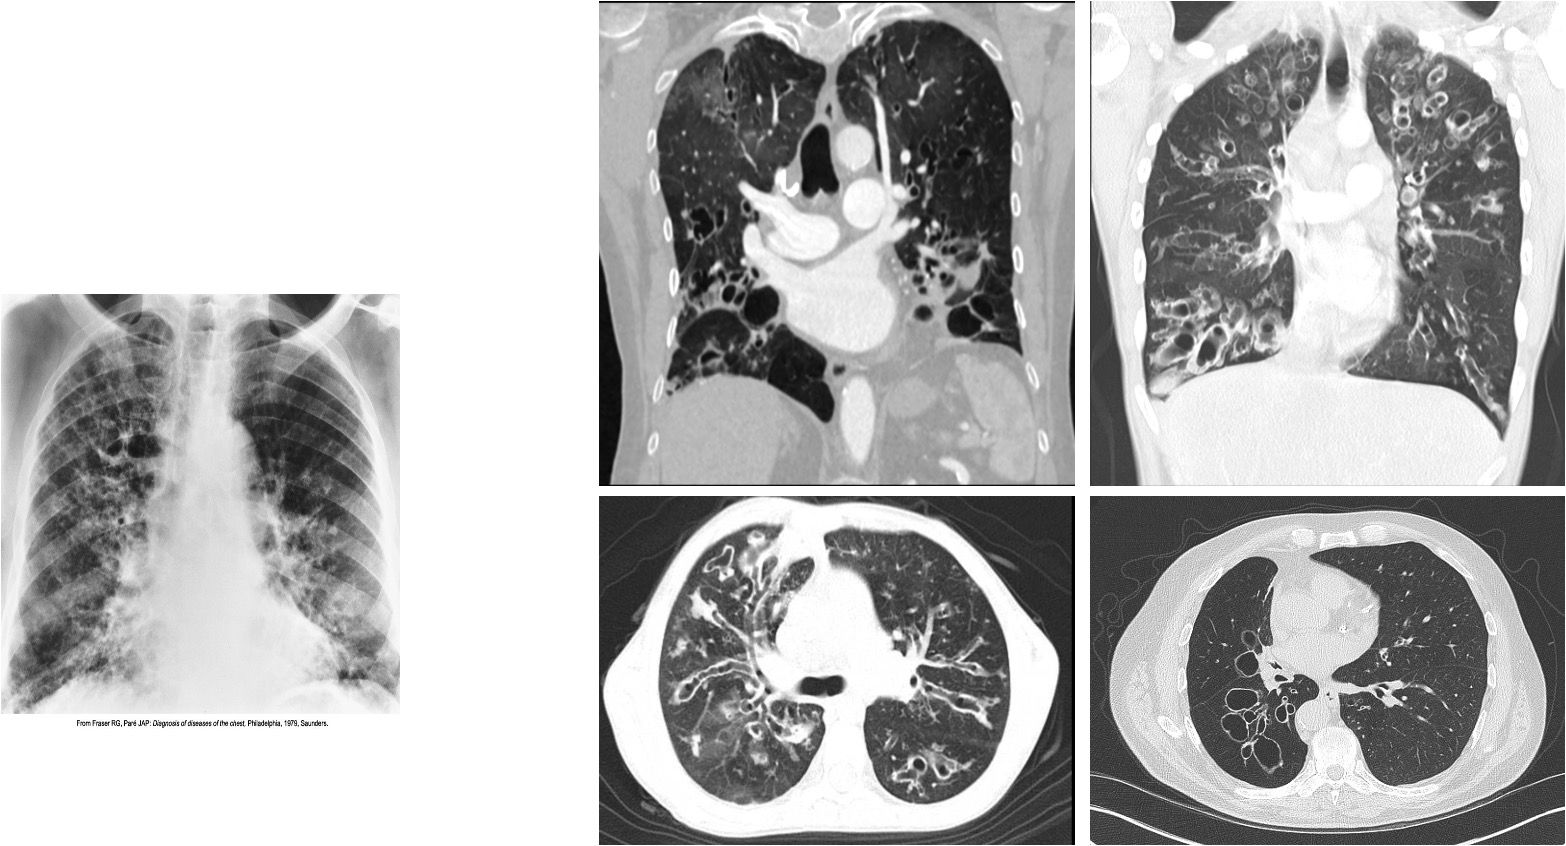

Bronchiectasis

Severe coarseninh of interstial markings involves the bases and right upper lobe

oval and circular cystic spaces, which resembles a honeycomb-like pattern, are best seen in the right upper lobe.